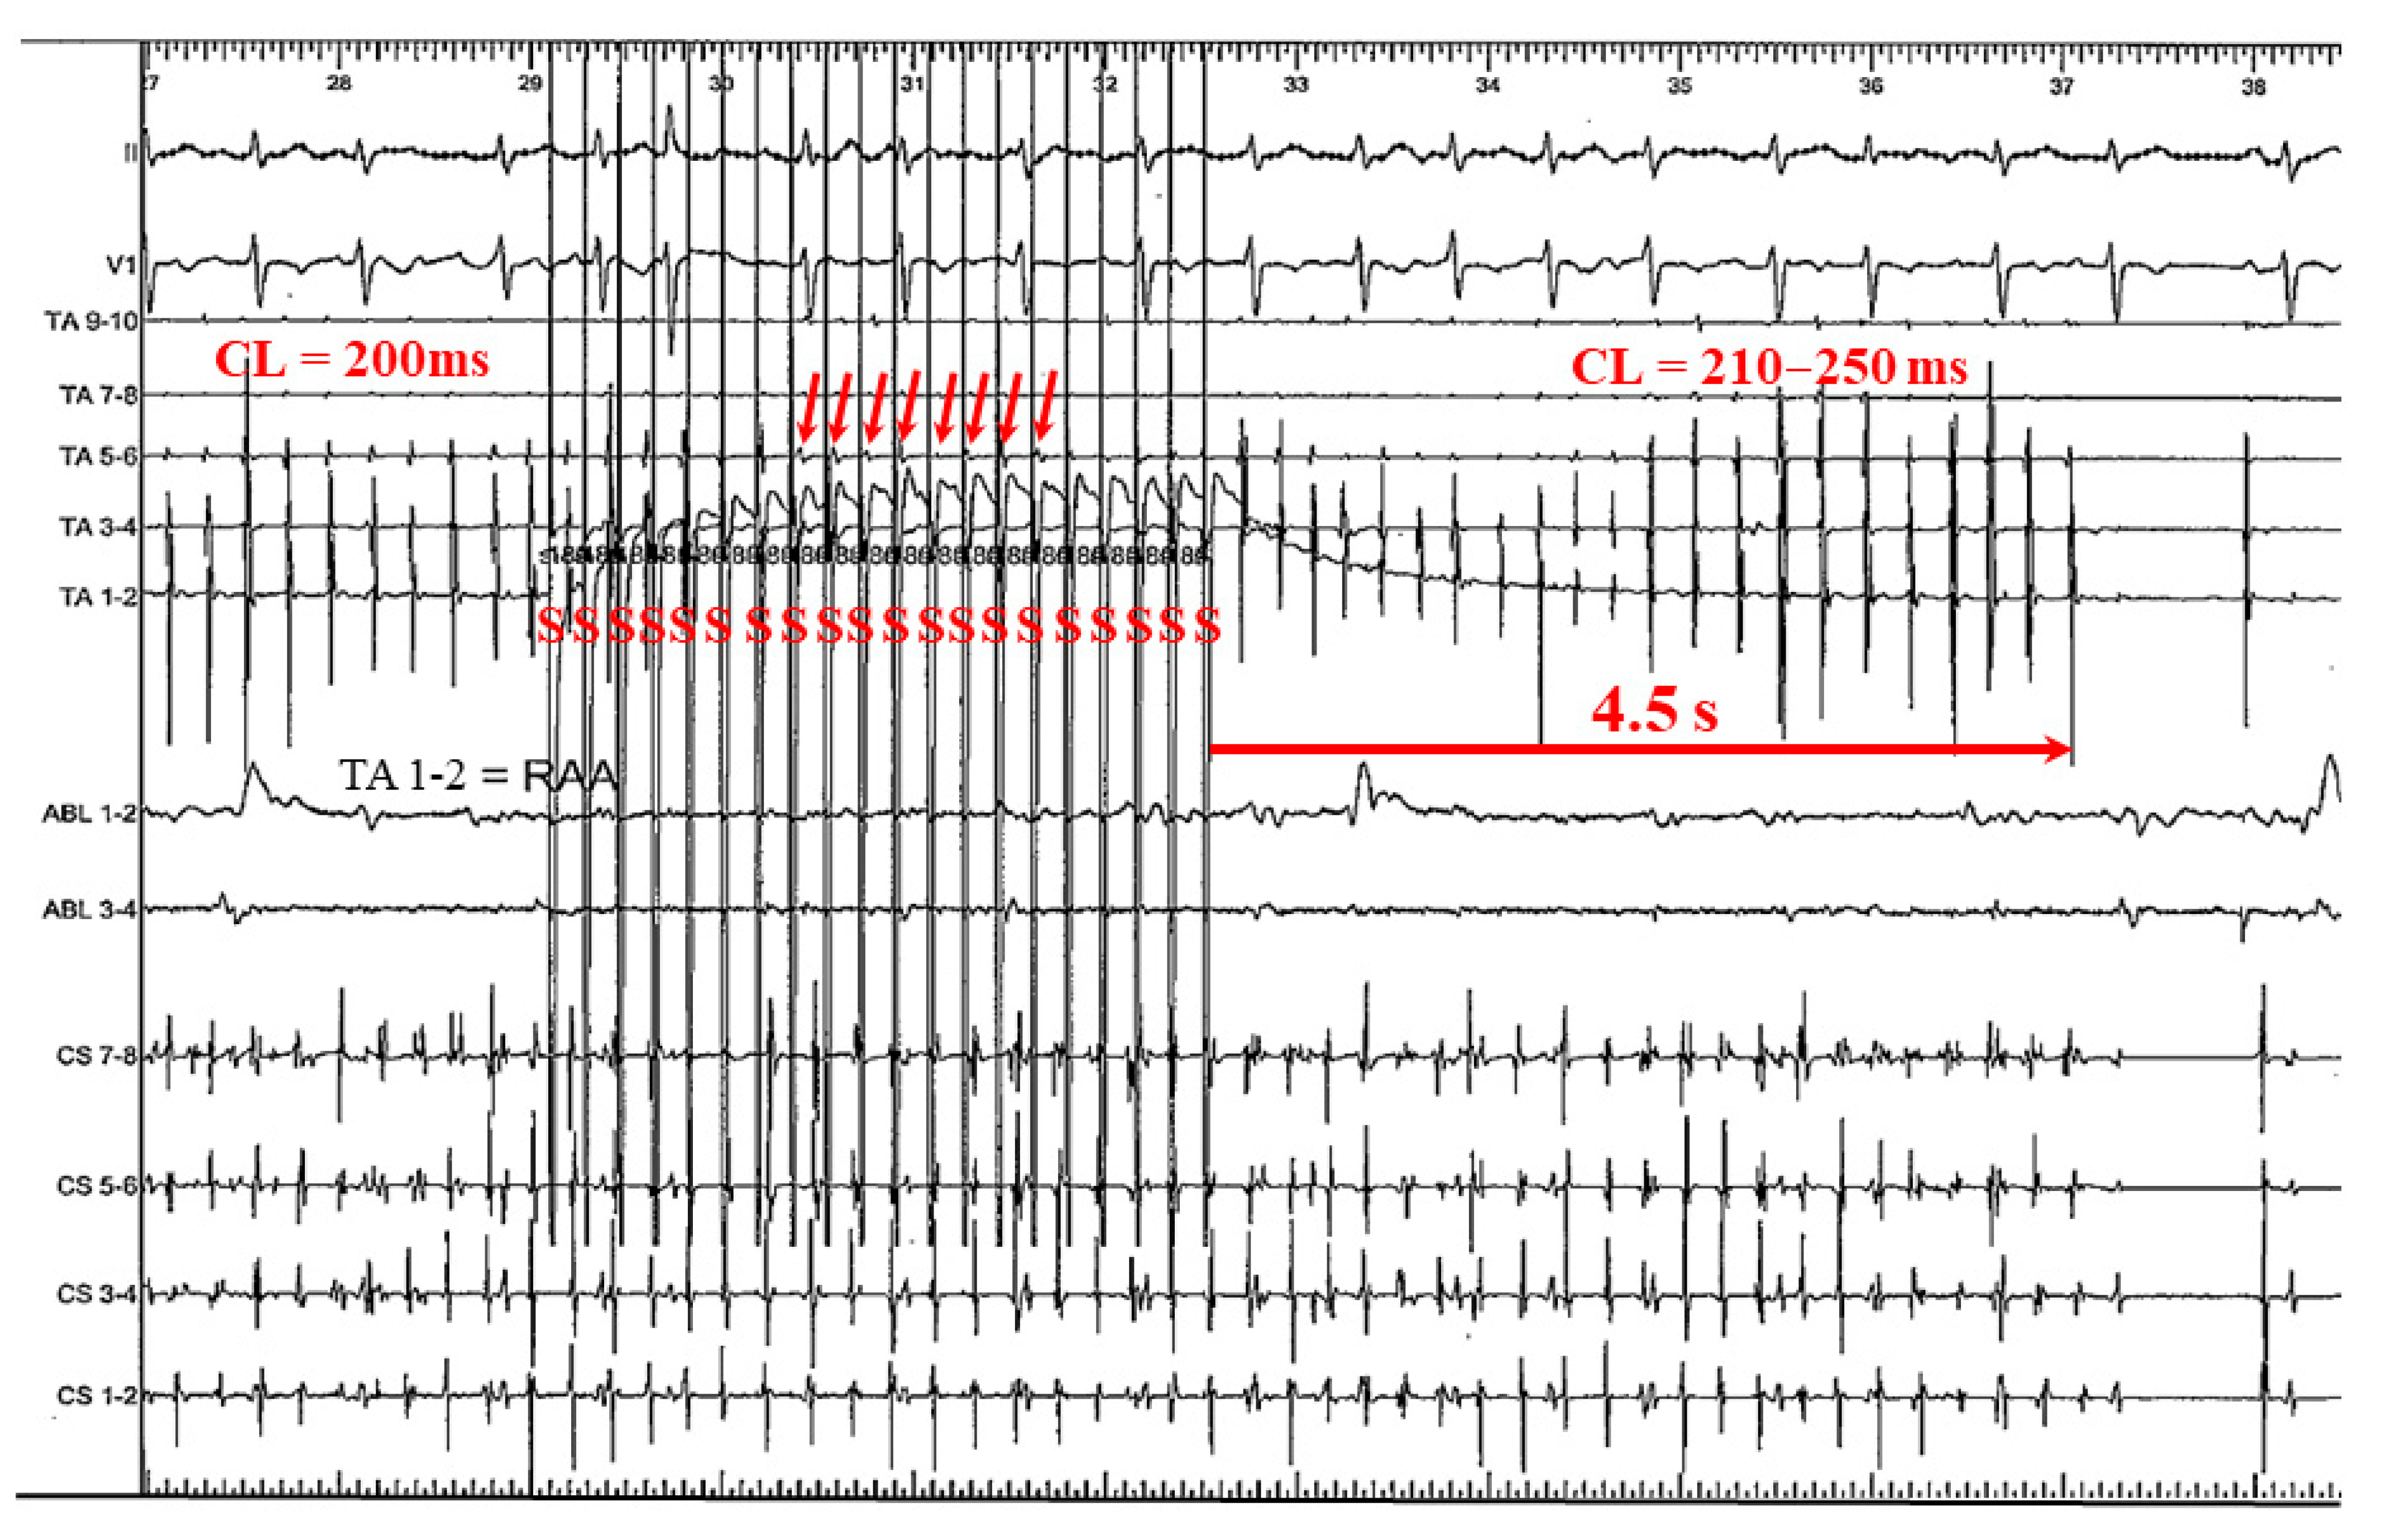

3.2.1. Case 1: 42-Year-Old Man with Symptomatic PAF

3.2.2. Case 2: 72-Year-Old Man with Symptomatic PAF